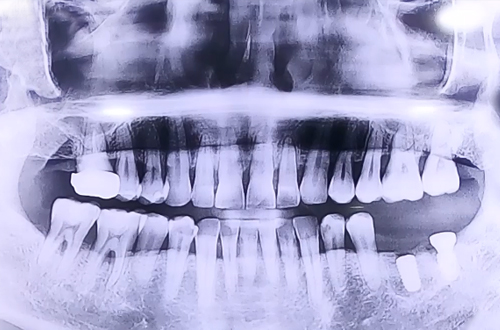

AFTER

맨 앞쪽에 발치 후 오랜 기간이 지난 큰 어금니 부위에는 자연 식립 임플란트를 진행해 드렸고

사랑니와 그로 인해 흔들림이 심했던 큰 어금니를 둘 다 발치한 뒤에 원래 있어야 하는 자리에

뼈이식과 임플란트를 동시에 진행하며 반듯하게 심어 뚜껑을 덮어 마무리해 드렸습니다.